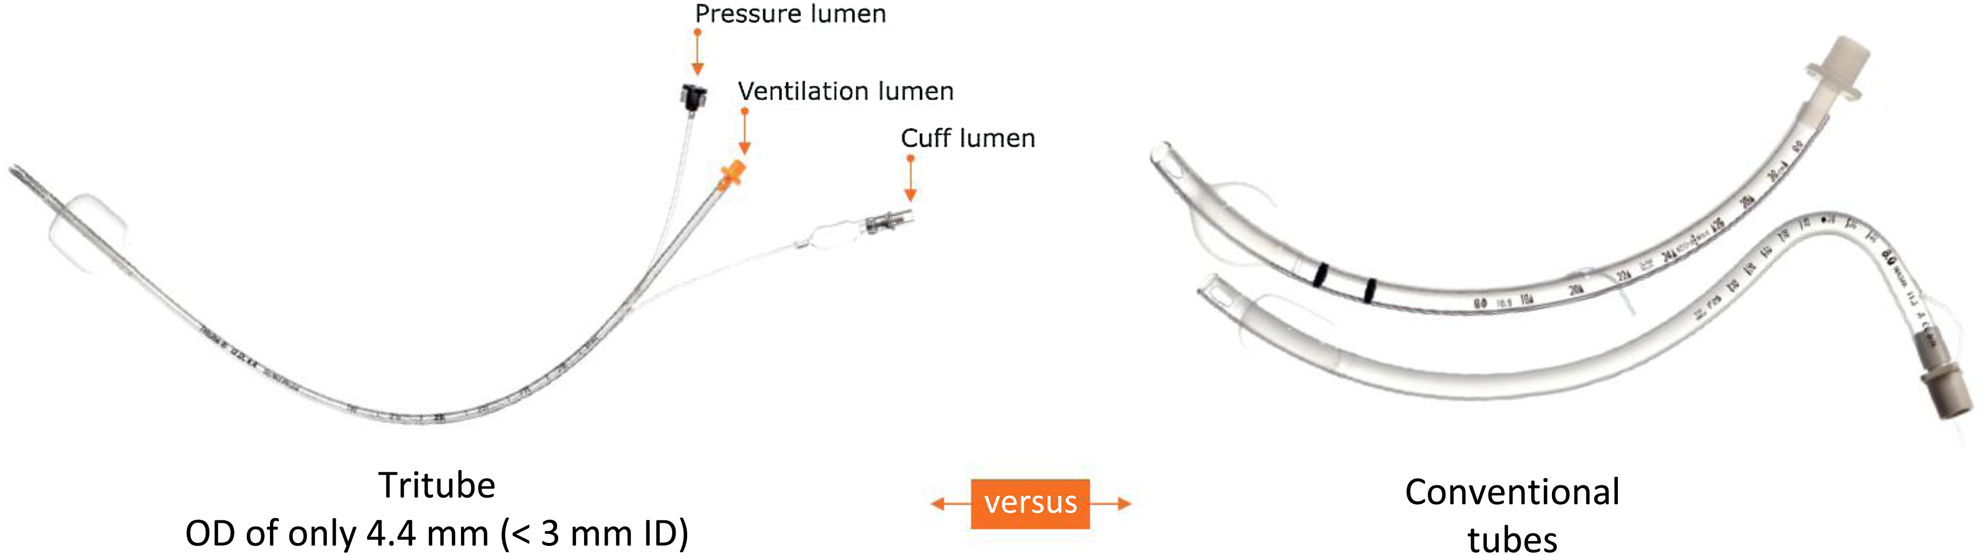

Endotracheal intubation may be hampered by intralaryngeal malignancies or stenosis. In addition, a tube obstructs the surgical field during laryngeal surgery and a (temporary) tracheostomy may be necessary. In patients with benign or low-grade malignant laryngeal tumours such as laryngeal carcinoma, a tracheostomy may be avoided if adequate ventilation can be achieved through an ultrathin endotracheal tube (ETT), which allows surgical visibility. The Tritube (Ventinova Medical, Eindhoven, the Netherlands) is a new tracheal tube (outer diameter, 4.4 mm), which consists of three lumina: a ventilation lumen (2.4 mm diameter), a cuff lumen and a pressure measurement lumen (Figure 1). Because of this small lumen, ventilation is achieved using flow-controlled ventilation with the Evone system (Ventinova Medical). It actively manages the inspiration and expiration, and is able to measure the intratracheal pressure using the extra lumen. Multiple articles have described its advantages over other ventilating methods.Reference Schmidt, Günther, Weber, Wirth, Brandes and Barnes2,Reference Schmidt, Günther, Weber, Kehm, Pfeiffer and Becker3

Fig. 1. The Tritube in comparison to conventional endotracheal tubes. Reproduced with permission from Ventinova Medical. OD = outer diameter; ID = inner diameter